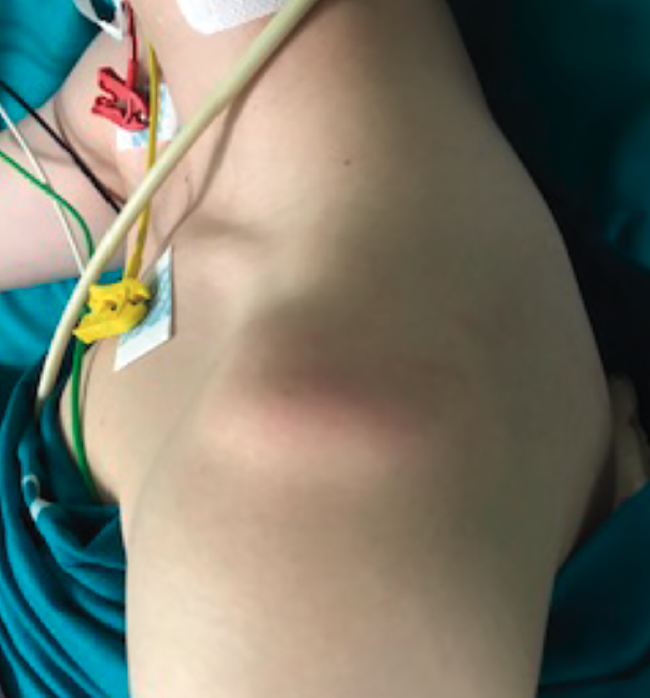

The procedure is generally performed under general anesthesia and brachial plexus block. It is advisable to carry out an exploration of the shoulder under anesthesia, since this allows us to evaluate the glenohumeral joint with muscle relaxation and clinically confirm the instability, as well as its type and grade.

The patient may be placed in a deck chair or in lateral decubitus, depending on the preference of the surgeon. We start by inserting a 30º arthroscope through a standard vision posterior port. Systematic exploration of the glenohumeral joint is very important for establishing a firm diagnosis of all the lesions, evaluating possible detachments of the anterior labrum, capsular tears, upper labral lesions and biceps lesions, bone damage including Bankart bone lesions and HSLs, rotator cuff disease and alterations of the inferior part of the capsular recess in order to discard humeral avulsion of the inferior glenohumeral ligament.